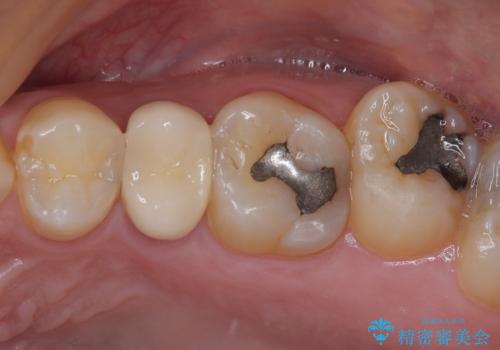

インプラント処置は、抜歯即時埋入を行い、十分な安定性が確認できたため、当日仮歯を装着しました。

インプラントが生着するのを待っている間に反対側の根管治療を行い、左右同時に補綴治療を行いました。